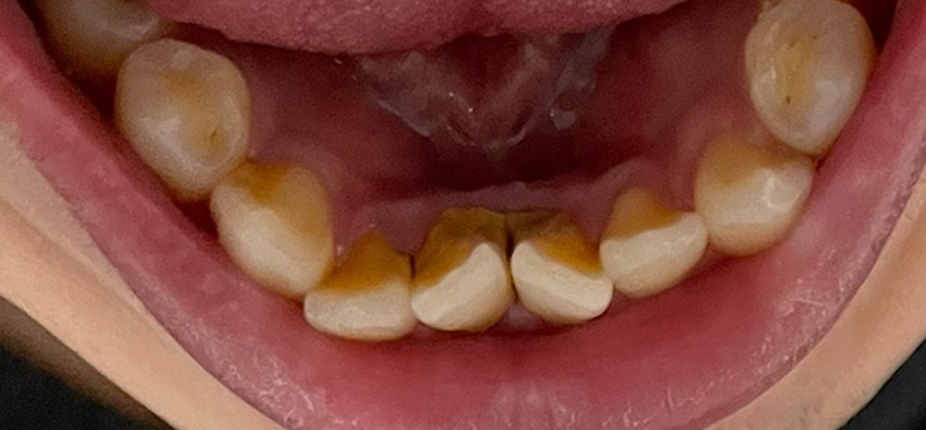

저는 치석이 주로 앞니 안쪽 편에 많이 있었는데요. 제 치석 사진입니다. (혐 주의)

병원에서 편안하게 스케일링을 해 주셔서 치석을 제거할 수 있었습니다.

아쉽게도 치석 떨어지고 나서 사진을 안 찍었었네요. 무슨 금속 덩어린 줄 알았었습니다 ^^;

큰 덩어리가 떨어지고 나니 치석 빠진 부분이 허전해서 한동안 뭔가 되게 허전한 느낌이었습니다. 그리고 잇몸이 올라오기 전까지는 구멍이 나 있었는데 다행히도 잇몸이 올라와서 메워지더군요.